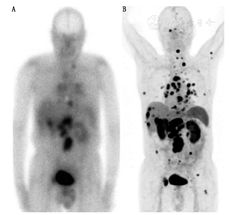

GEP NETs患者的管理取决于肿瘤的分级和SSTR表达。分子成像有助于检测肿瘤的异质性,并指导临床医师寻求最佳的治疗方案。此外,肿瘤分级和放射性标记的SSAs(或18F-FDOPA)及18F-FDG PET/CT功能显像结果之间存在潜在的翻转现象。放射性标记的SSAs(或18F-FDOPA)高摄取和18F-FDG低摄取的不匹配被广泛认为是低级别GEP NETs功能显像表现形式;相反,放射性标记的SSAs(或18F-FDOPA)低摄取和18F-FDG高摄取则提示高级别肿瘤(图7)。